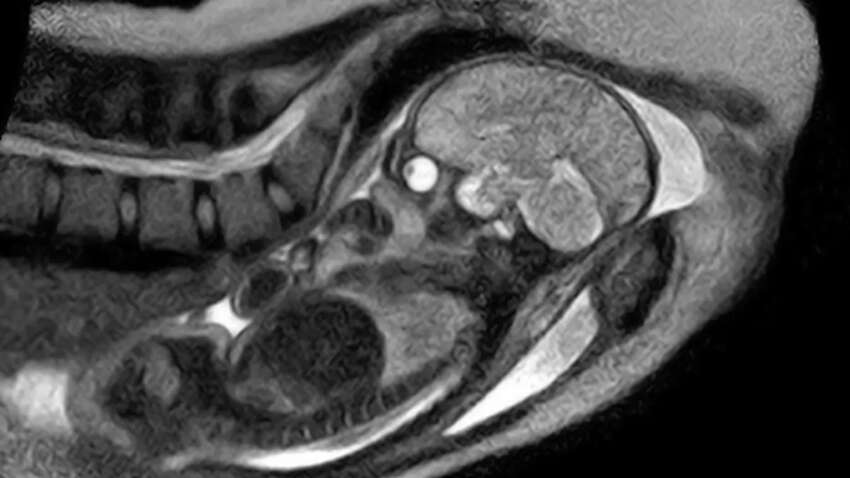

Впервые в истории женщина в Германии согласилась рожать в аппарате МРТ, чтобы ученые могли в реальном времени увидеть, как проходит этот сложный физиологический процесс. Исследование возглавил доктор медицины Кристиан Бамберг из университетской клиники "Шарите" в Берлине. Результаты были опубликованы в статье "Наблюдение за рождением человека посредством открытой магнитно-резонансной томографии в режиме реального времени".

Последние 45 минут родов зафиксировали серией снимков МРТ, которые впоследствии смонтировали в 25-секундное ускоренное видео. На нем видны финальные схватки, движения внутренних органов матери и появление головки ребенка. Запись позволила медикам впервые с высокой точностью увидеть положение плода и его путь через родовые пути.